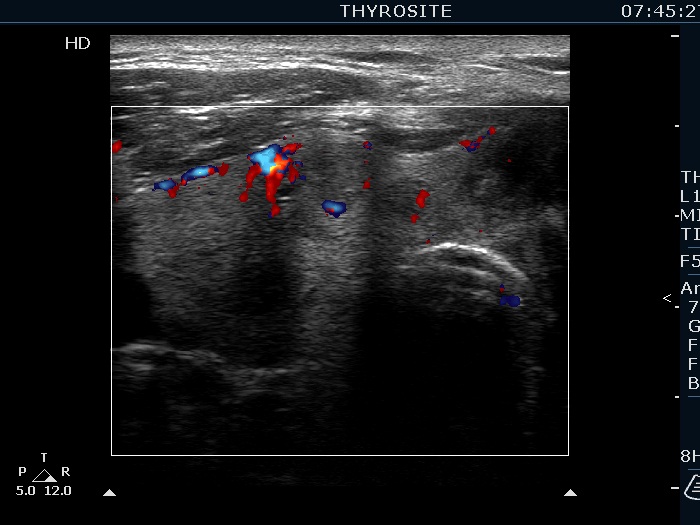

Ultrasonography. The right lobe was echonormal and presented several hypoechoic nodules. A large, inhomogeneous, partly deeply hypoechoic, partly minimally hypoechoic or echonormal mass occupied the left lobe. The borders of the tumor were irregular. There were multiple lymph nodules upper and lateral to the left thyroid lobe. The nodes had a heterogeneous pattern and lacked hilum. The vascularity was scanty both in the thyroid nodules and the lymph nodes.